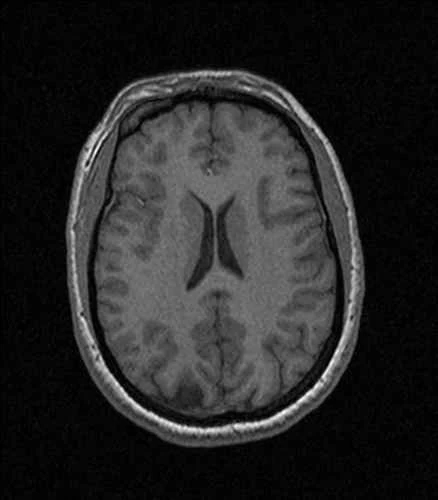

By記事2026-01-03 研究者は脳スキャンを使って思考を言葉に変換する <img width="575" height="536" loading="lazy" src="/upload/20260103/82a99db349a1ac.webp" alt="" class="wp-image-153829" sizes="auto, (max-width: 575... 記事